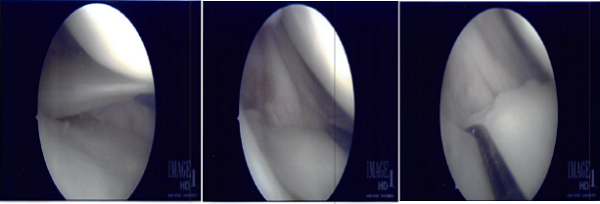

The lateral entry portal was made and the arthroscope was introduced. The Patellofemoral joint and the medial compartment was examined and there was near complete tear of the posterior horn of the medial meniscus from the capsule. The decision to repair it was taken.

The margins were probed using rasp and shaver. The meniscus was approximated onto the capsule and fixed using FasT-Fix Nephew curved x2. Good opposition was achieved. The sutures were cut after the notch. All-inside technique was used. Lastly, in the intercondylar area the scope was moved, the ACL was found to be intact.